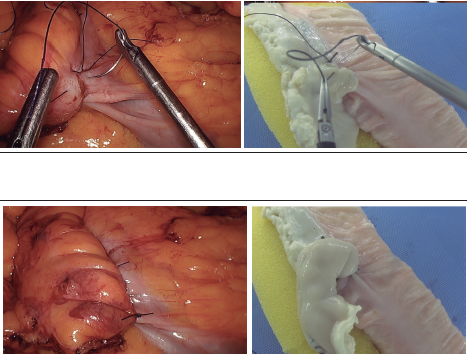

Imágenes y Cirugía

Mauricio Gonzalez-Urquijo